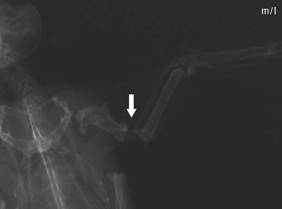

Radius fracture,

dislocated |

Radius fracture

after intramedullary pinning with a 0.4 mm

cannula |